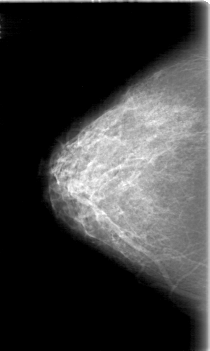

D_4058_1.RIGHT_MLO

RIGHT_MLO LINES 5266 PIXELS_PER_LINE 3361 BITS_PER_PIXEL 12 RESOLUTION 43.5 NON_OVERLAY